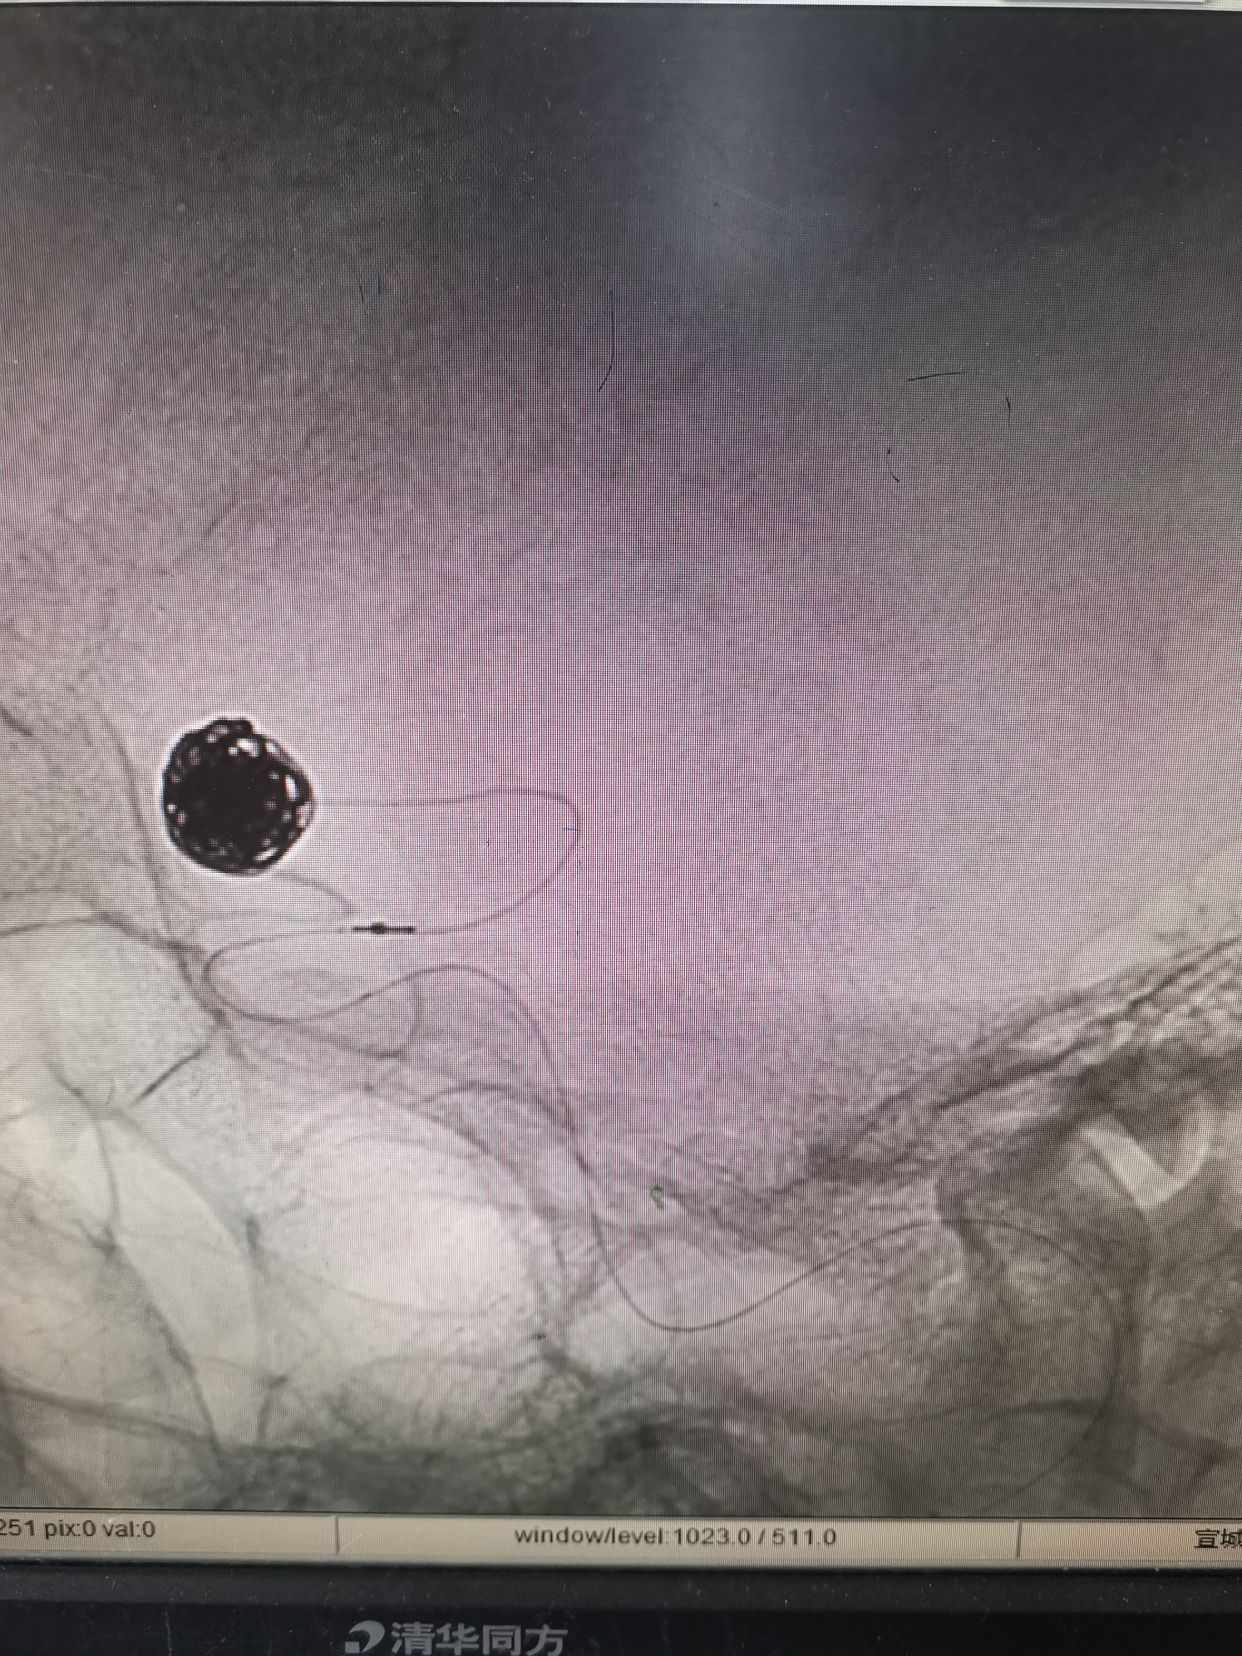

微导管到位后,填入Cosmos Complex 7mm/22cm

继续填入Complex 6mm/26cm

继续填入Complex 6mm/18cm

继续填入Complex 5mm/15cm

术后动脉瘤不显影,双侧大脑前显影。右侧略差。